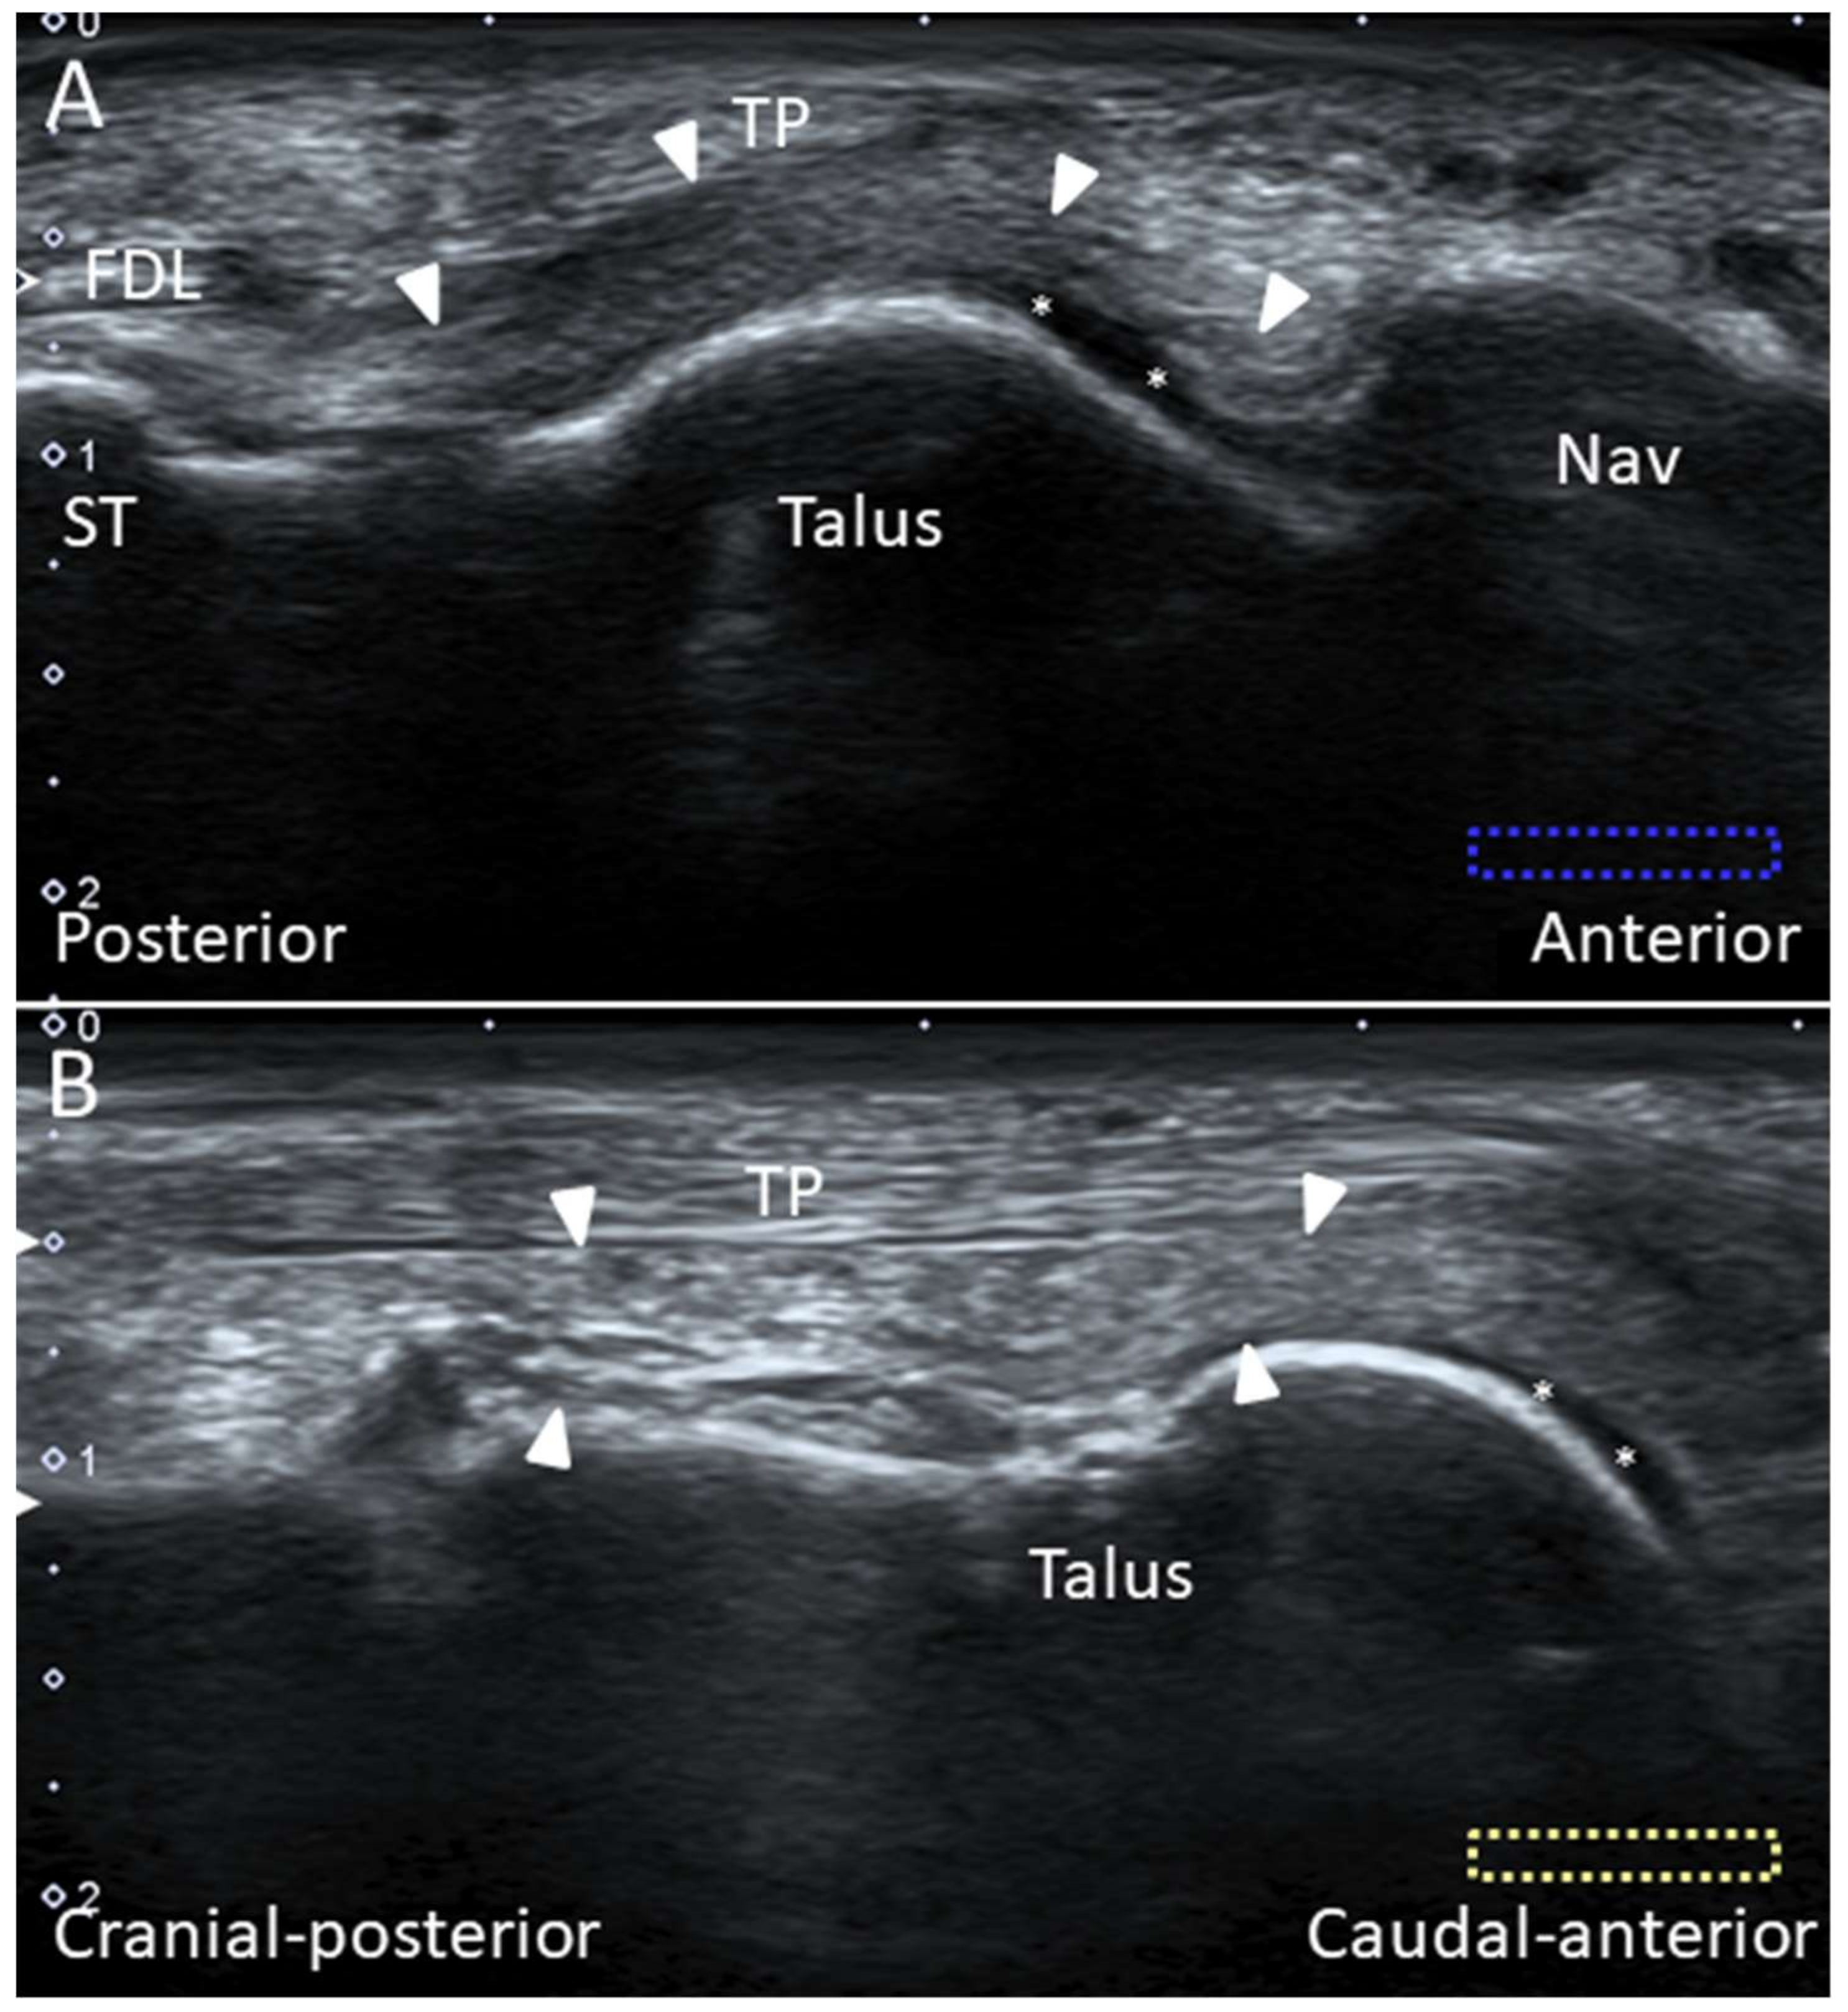

4.3. Tibialis Posterior Tendon

4.3.1. Anatomy

4.3.2. Scanning Technique

4.3.3. Clinical Relevance